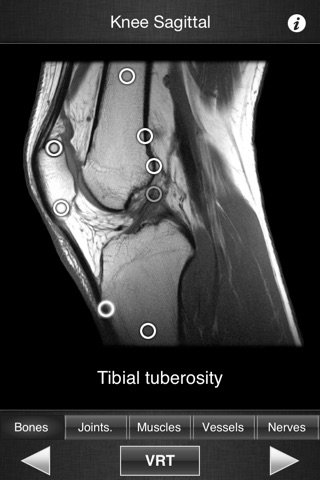

This application is designed for healthcare professionals (Radiologists, General Practitioners, Orthopedists, Surgeons, Physiotherapists among others) as well for students, as a reference and learning tool. It contains 82 contiguous knee MR slices (4-5 mm thickness) in the three anatomical planes.

- Fluid display of images in the three anatomical planes.

- 3D Image volume (VR) allows precise location of slice position.